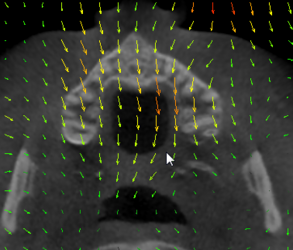

- Improved integration of non rigid deformations, including grid (displacement field) and bspline transforms

- Interactive application of non rigid deformations to volume slices, models, markups

- Visualization of any transforms as glyphs, grid, or contours in 2D slice and 3D views - click here for demo video

- Computing and applying inverse transforms, compositing any number of transforms

- Real-time update: if the transform (or any visualization parameter) is changed then the visualization is updated immediately (interactive visualization while editing the transform)